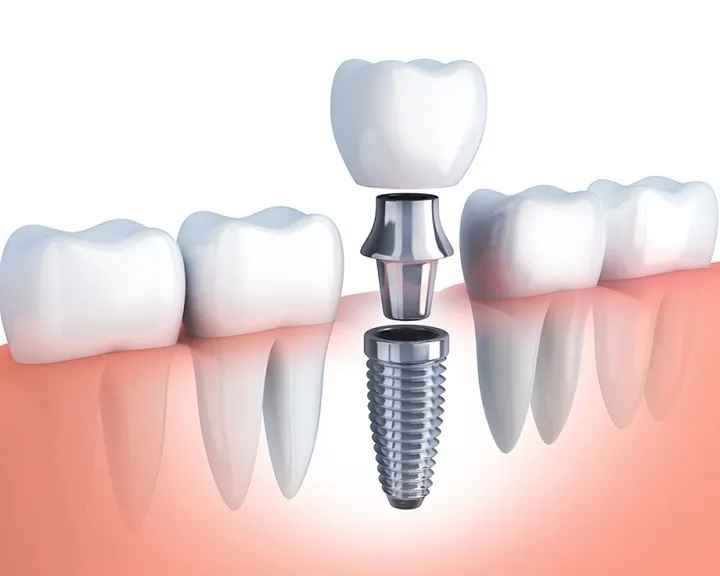

Bọc răng sứ là một phương pháp phục hồi và nắn chỉnh răng hiệu quả trong nha khoa. Phương pháp này sẽ sử dụng một mão sứ gắn lên phần răng bị khuyết và hư hỏng. Thông thường, mão sứ sẽ được chế tạo hoàn toàn bằng sứ tinh khiết 100%. Tuy nhiên, một số loại mão sứ tối ưu chi phí thường sẽ kết hợp với kim loại. Phương pháp này giúp phục hồi bề mặt, màu sắc, vẻ đẹp thẩm mỹ. Đồng thời cải thiện hiệu quả chức năng ăn nhai của răng.

Trước khi thực hiện bọc răng sứ, bác sĩ sẽ tiến hành mài nhỏ cùi răng. Việc này sẽ hỗ trợ quá trình thông qua việc tạo ra một nền tảng vững chắc cho mão sứ. Sau đó, mão sứ sẽ được lắp vào răng đã được mài.

Khác với niềng răng, phương pháp bọc răng sứ tác động trực tiếp lên bề mặt răng tự nhiên. Ngoài ra, phương pháp này có thể được thực hiện theo hai kỹ thuật chính. Đó là kỹ thuật mài cùi răng và kỹ thuật lắp mão răng sứ. Quá trình này giúp lớp mão răng sứ mới đặt lên các răng bị thiếu sót một cách chắc chắn và tối ưu nhất. Từ đó mang lại sự hoàn thiện và tự tin cho nụ cười của bệnh nhân.